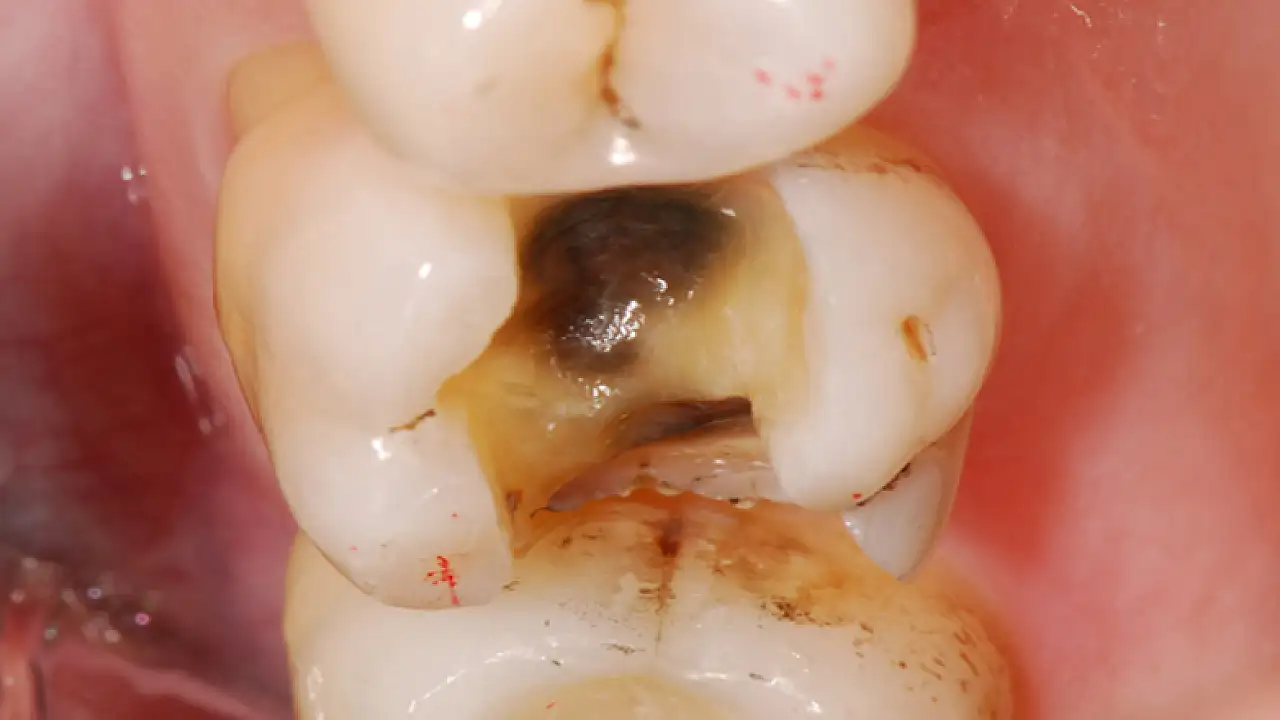

Çürük diş kalbe zarar veriyor

İlker Arslan, “Güzel ve sağlıklı dişlerin,estetik avantajlarının yanı sıra genel vücut sağlığımıza da olumlu etkisi vardır. İhmal edilen küçük bir çürük, romatizmaya, ülsere, böbrek, kalp-damar hastalıklarına ve karaciğer sorunlarına, hatta kansere bile neden olabilmektedir” dedi.

Ülkemizde maalesef "diş hekimine" 6 ayda bir gitmek zorunluluğu varken 2 yılda bir diş hekimine gidildiğini belirten Dt. İlker Arslan, “İleride oluşabilecek sistematik rahatsızlıkların önüne geçebilmek için ağız ve diş bakımını düzenli yapmak, koruyucu ve önleyici tedavileri yaptırmak gerekmektedir” diye konuştu.